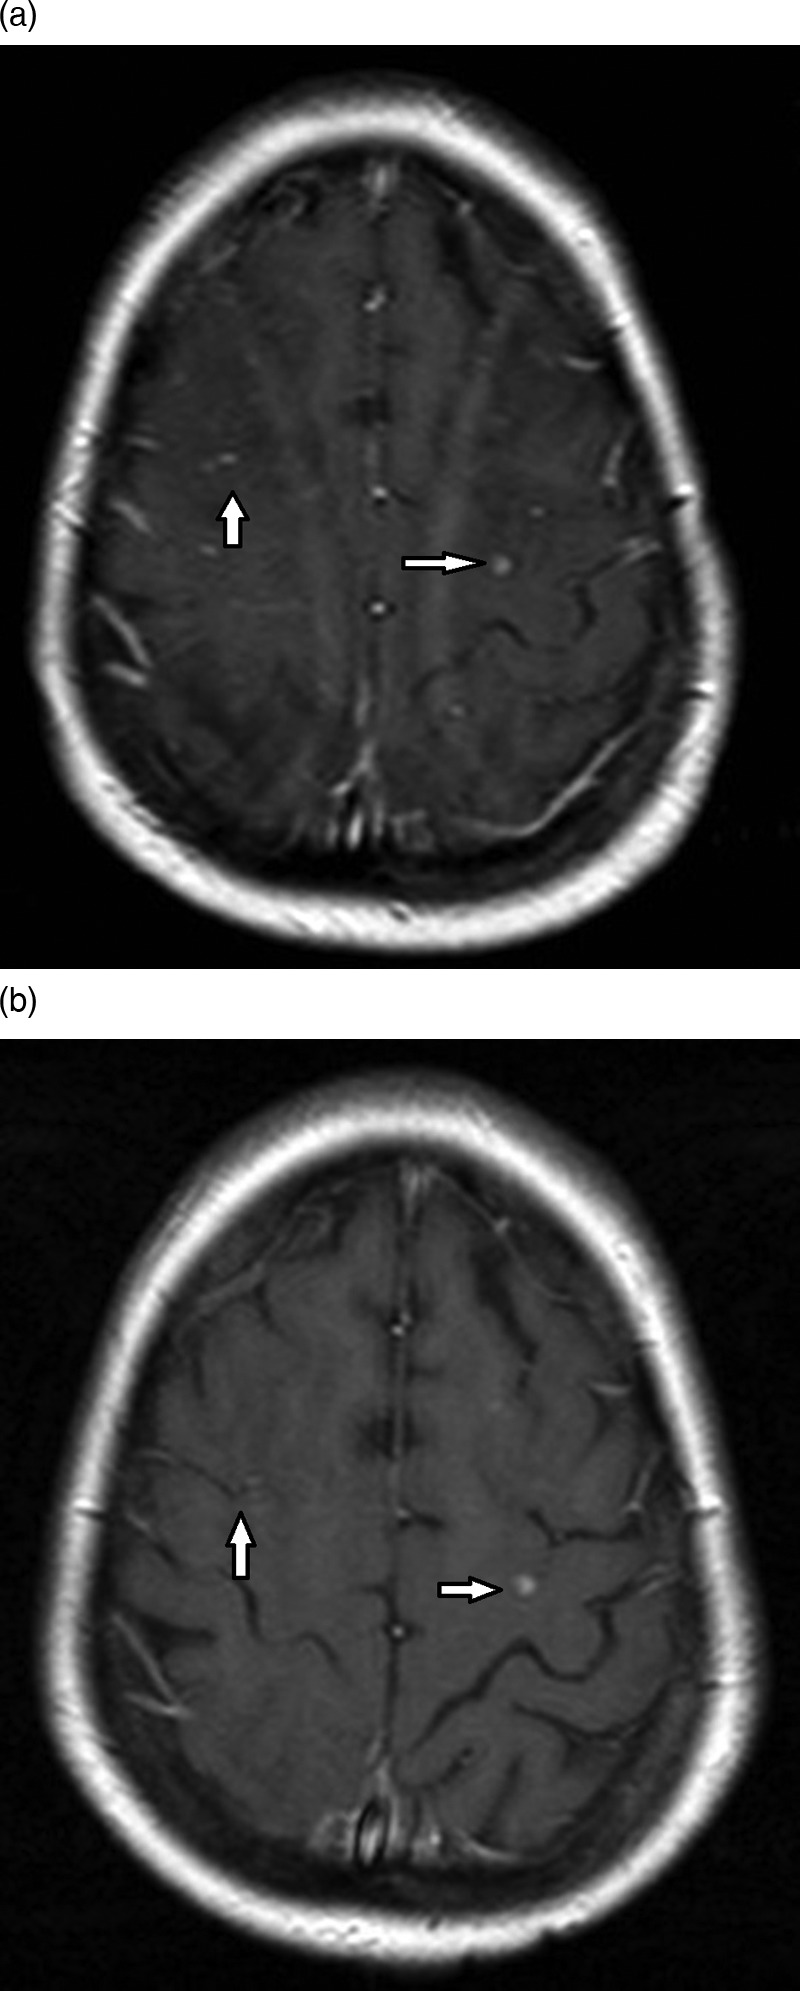

Figure 2.

Axial fluid attenuation inversion recovery (FLAIR) MRIs at the level of the centrum semiovale (A) and at the level of the cerebellum (B). A follow-up 6 days later (A and B) showing decrease and resolution of the symmetrical abnormal high FLAIR signal.